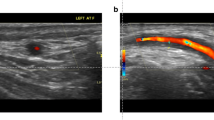

A 25 year-old Middle Eastern male with a 6 year history of recurrent deep venous thrombi despite therapeutic anticoagulation presented to a vascular medicine specialist . Physical examination demonstrated painful erythematous lesions over the lateral aspect of the calf (A, Courtesy Dr. Steven Dean) and oral ulcerations. B. Subsequent contrast-enhanced magnetic resonance venogram showed occlusion of a previously placed filter in the inferior vena cava (arrowhead). Extensive venous collaterals are evident. C. Coronal plane post-contrast volumetric interpolated breathhold T1-weighted image shows signal void delineating the IVC filter (arrows).